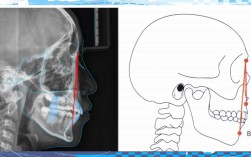

答:可通过以下方法初步判断:①观察牙齿是否明显重叠、扭转或“大小不一”;②查看牙弓是否狭窄,前牙是否“拥挤外凸”;③咬合时后牙是否能完全接触,前牙有无深覆牙合(上牙盖下牙过多)或深覆盖(上牙前突);④刷牙时是否频繁感到拥挤区食物嵌塞,若存在以上情况,建议拍摄口腔全景片、头颅侧位片,由正畸医生测量拥挤度并评估。